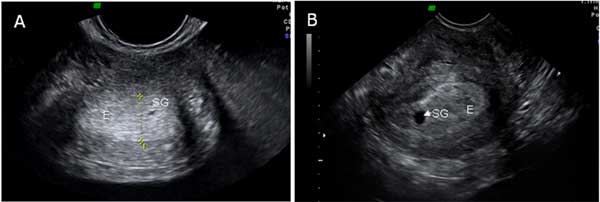

La primera estructura detectable por ecografía es el saco gestacional. Aparece como una pequeña esfera de líquido, con los bordes muy marcados, dibujándose en el espesor del endometrio. Suele crecer un milímetros por día. Con los mejores ecógrafos y en condiciones favorables, puede verse en la semana cuatro y dos días, cuando mide tan sólo 2 milímetros de diámetro.

Podemos ver dos sacos gestacionales (en ambas imágenes, con las siglas SG) de 1 y 7 milímetros (4,1 y 4,4 semanas). Son las primeras estructuras del embarazo que se identifican por ecografía. Tienen forma de pequeñas esferas llenas de líquido, que se hacen visibles en el espesor del endometrio (E). En su interior acabará visualizándose el embrión.